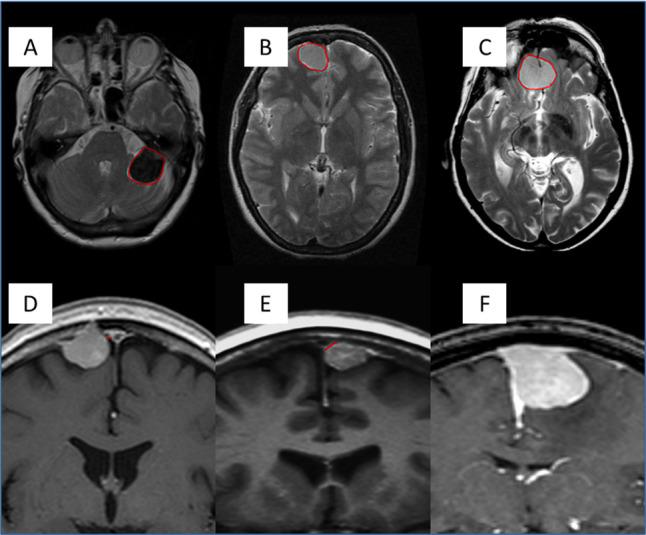

Due to the increased use of CT and MRI, the prevalence of incidental findings on brain scans is increasing. Meningioma, the most common primary brain tumour, is a frequently encountered incidental finding, with an estimated prevalence of 3/1000. The management of incidental meningioma varies widely with active clinical-radiological monitoring being the most accepted method by clinicians. Duration of monitoring and time intervals for assessment, however, are not well defined. To this end, we have recently developed a statistical model of progression risk based on single-centre retrospective data. The model Incidental Meningioma: Prognostic Analysis Using Patient Comorbidity and MRI Tests (IMPACT) employs baseline clinical and imaging features to categorise the patient with an incidental meningioma into one of three risk groups: low, medium and high risk with a proposed active monitoring strategy based on the risk and temporal trajectory of progression, accounting for actuarial life expectancy. The primary aim of this study is to assess the external validity of this model.

IMPACT is a retrospective multicentre study which will aim to include 1500 patients with an incidental intracranial meningioma, powered to detect a 10% progression risk. Adult patients ≥16 years diagnosed with an incidental meningioma between 1 January 2009 and 31 December 2010 will be included. Clinical and radiological data will be collected longitudinally until the patient reaches one of the study endpoints: intervention (surgery, stereotactic radiosurgery or fractionated radiotherapy), mortality or last date of follow-up. Data will be uploaded to an online Research Electronic Data Capture database with no unique identifiers. External validity of IMPACT will be tested using established statistical methods.